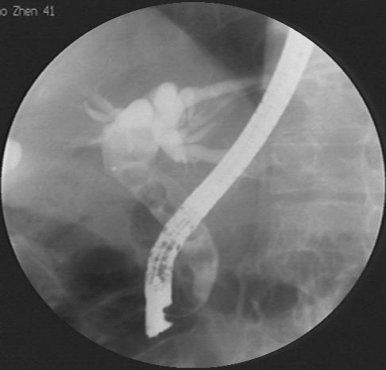

胃腸肝膽外科開展ERCP及取石術

我院胃腸肝膽外科與省立三院(原山東省交通醫(yī)院)合作(zuò)開展ERCP(經内鏡逆行胰膽管造影術)+十二指腸乳頭切開取石術。

優點:創傷小、手術時(shí)間(jiān)短、并發症少、安全性高等。這(zhè)種手術屬于微創手術,手術創傷非常小,不會給患者帶來(lái)太多的痛苦,術後恢複也(yě)比較快(kuài)。